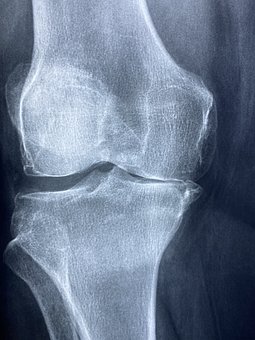

무릎 관절의 무릎 퇴행성 관절염의 진행 단계는 연골의 손상 정도에 따라 크게 4단계로 나눌 수 있습니다.

2 단계 연골이 손상돼 무릎 관절 사이 간격이 좁아지면 염증이 생겨 무릎을 자유롭게 구부리고 펴기가 어렵습니다.

4 단계말기 단계로 증상이 악화되면 연골 손상이 심하고 무릎 위아래 뼈가 거의 닿아 극심한 통증과 발열을 동반합니다. 한번 손상된 연골은 회복이 어려운 것이 사실입니다. 다만, 초,중반까지는 비수술적 치료를 통해 증상 개선을 기대할 수 있습니다. 따라서 의심 증상이 발생할 경우 조기에 전문의를 찾아 정확한 진단과 관리를 받는 것이 증상악화를 줄이는 무릎 퇴행성 관절염 치료의 핵심입니다.